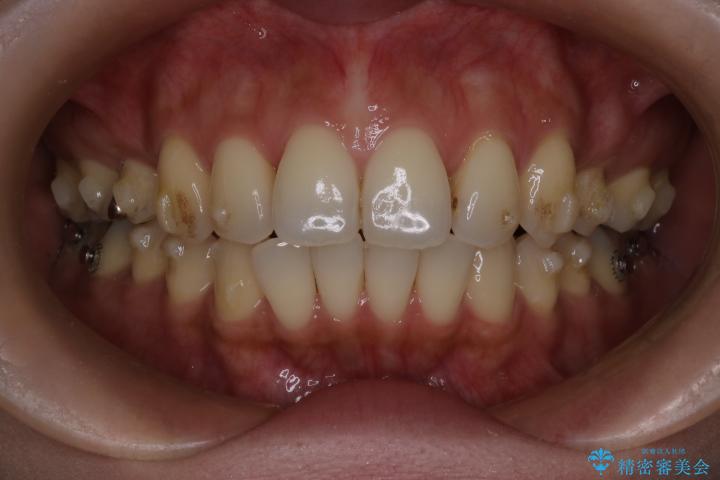

治療前

• 上顎前歯の突出を軽減 インビザラインによる抜歯矯正 治療前画像